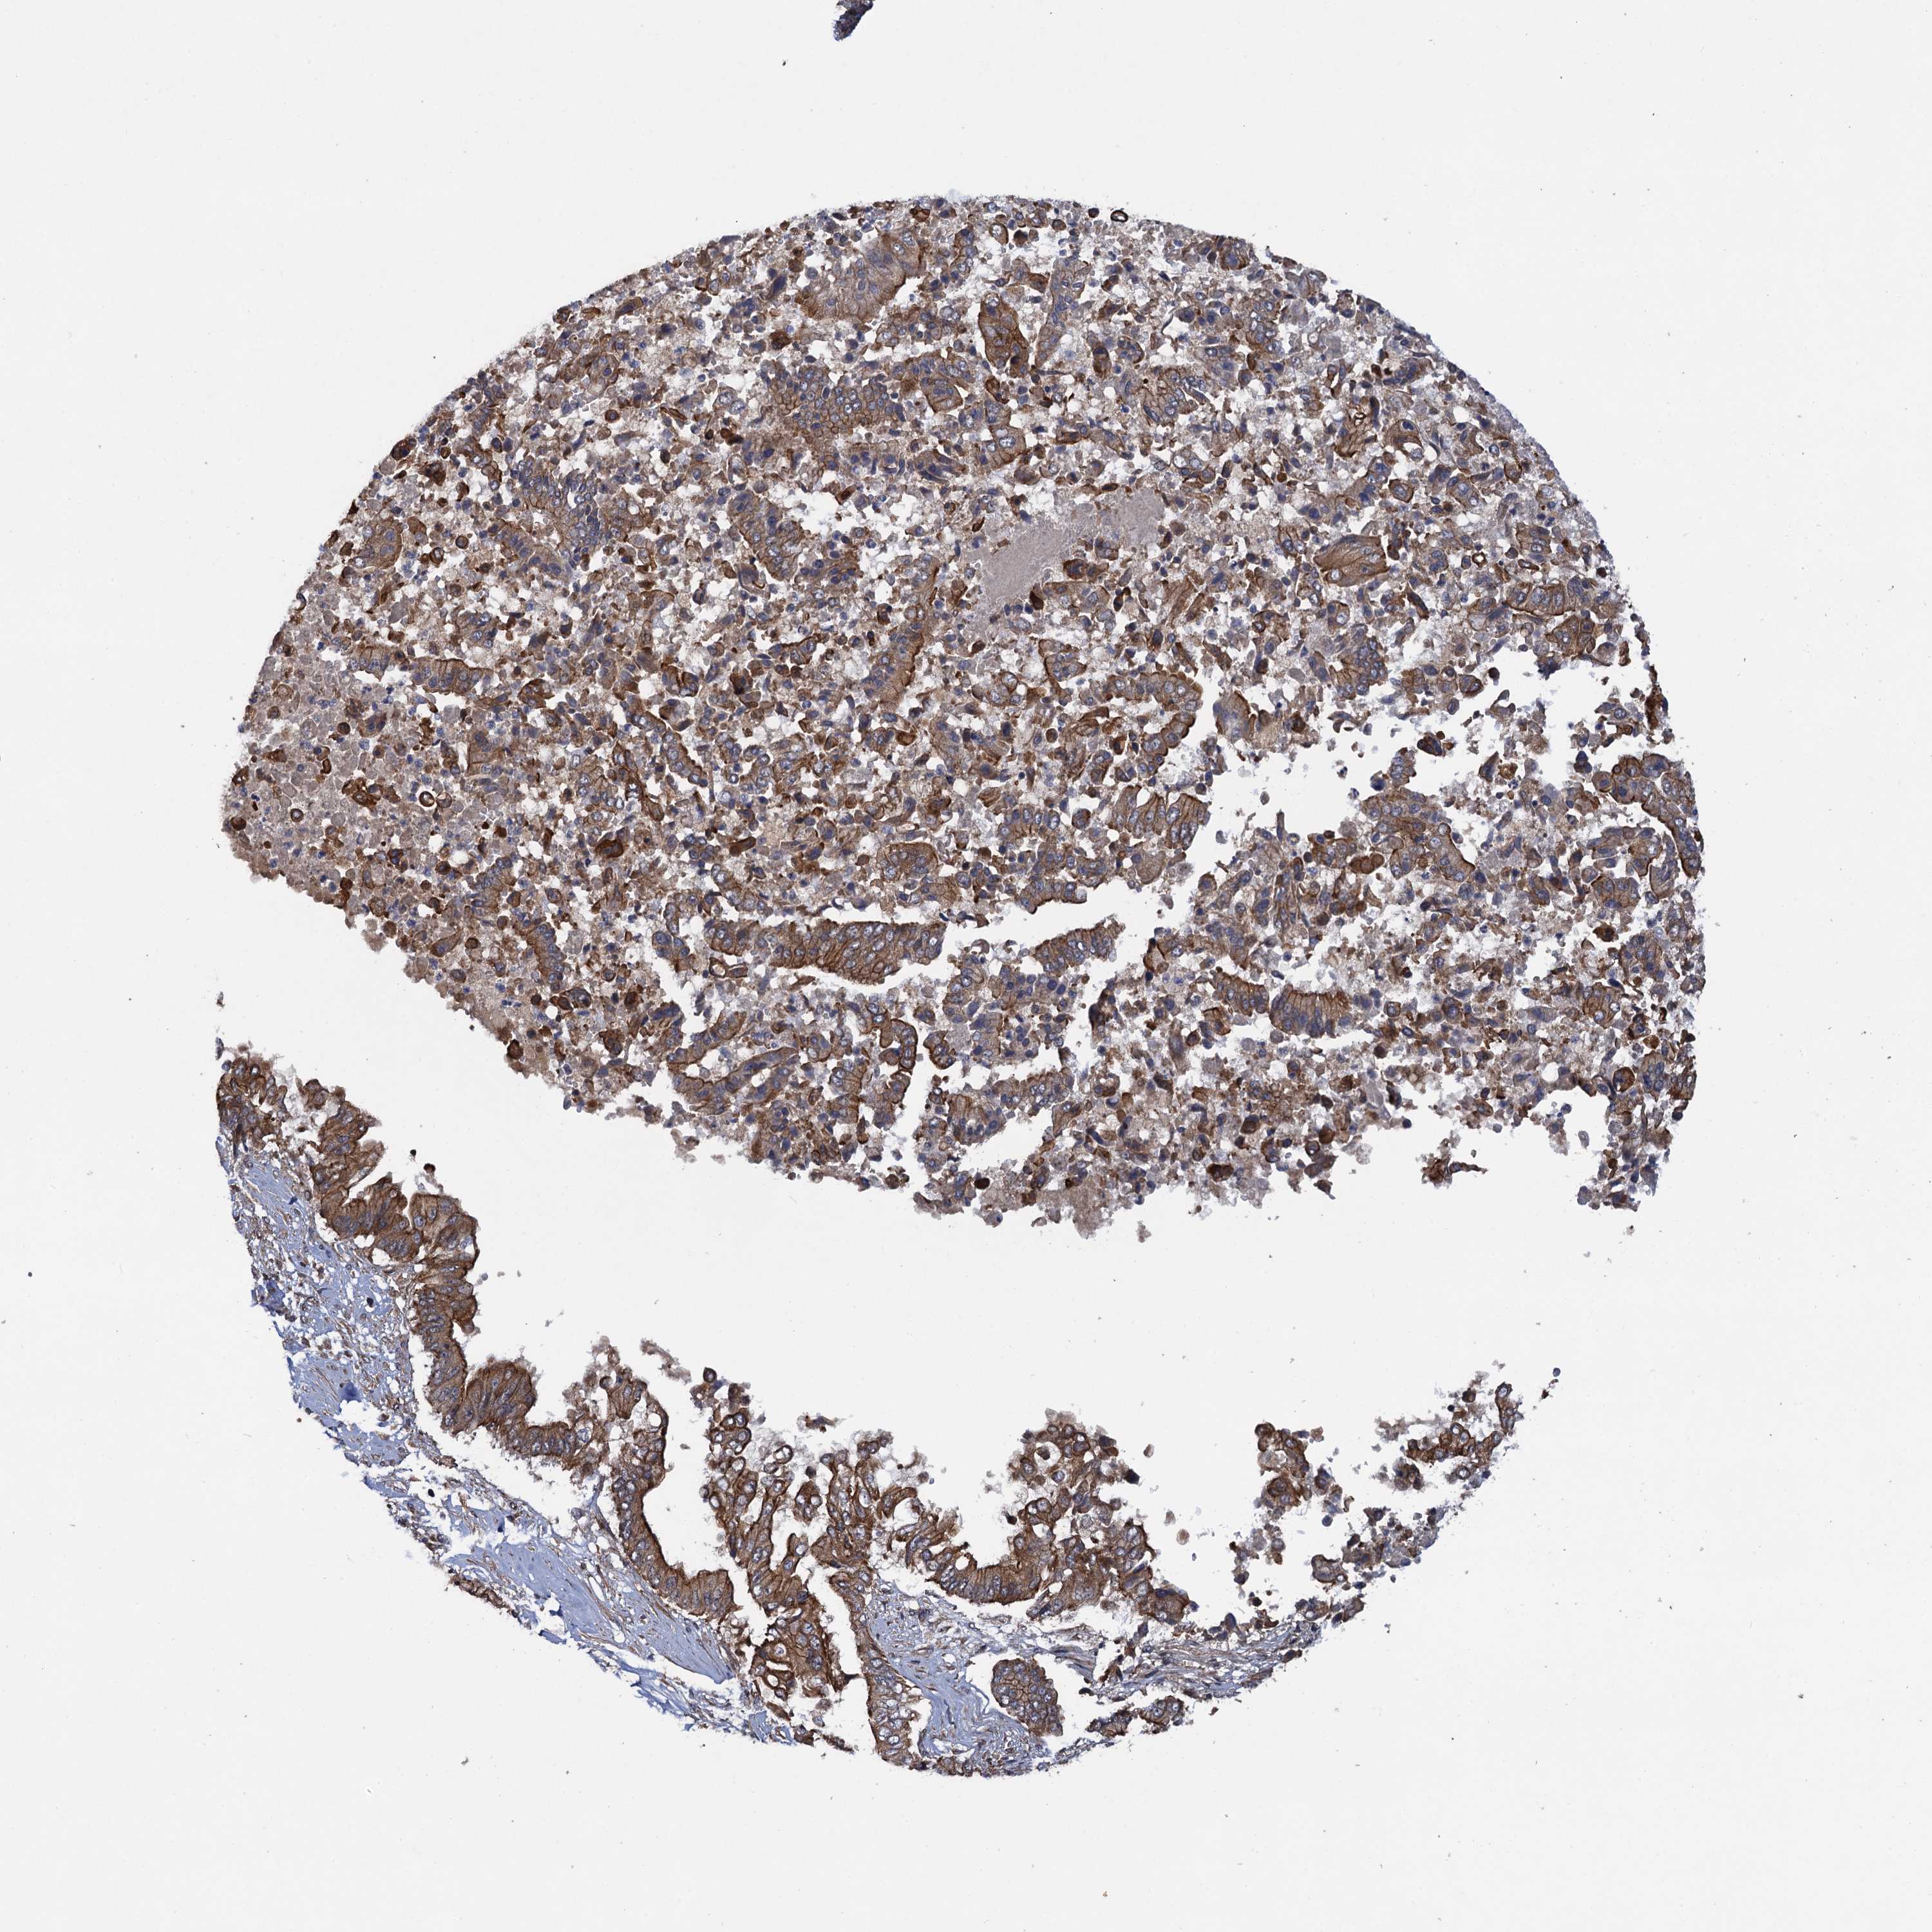

PANCREATIC CANCER - Protein expressioni

A mouse-over function shows sample information and annotation data. Click on an image to view it in a full screen mode. Samples can be filtered based on level of antibody staining by selecting one or several of the following categories: high, medium, low and not detected. The assay and annotation is described here.

Note that samples used for immunohistochemistry by the Human Protein Atlas do not correspond to samples in the TCGA dataset.

Antibody stainingi

Antibody staining in the annotated cell types in the current human tissue is reported as not detected, low, medium, or high, based on conventional immunohistochemistry profiling in selected tissues. This score is based on the combination of the staining intensity and fraction of stained cells.

Each image is clickable and will lead to virtual microscopy that enables deeper exploration of all samples and also displays staining intensity scores, fraction scores and subcellular localization as well as patient and tissue information for each sample.

Antibody HPA040601

Antibody HPA040652

Staining

High

Medium

Low

Not detected

Intensity

Strong

Moderate

Weak

Negative

Quantity

>75%

75%-25%

<25%

None

Location

Nuclear

Cytoplasmic/membranous

Cytoplasmic/membranous,nuclear

Adenocarcinoma, NOS